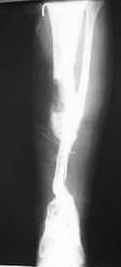

I would treat this patient with ilizarov trans osseous osteo synthesis with

distraction at two metaphyseal corticotomies.the reasons being

1.the patient can start to weight bear fully straightaway!

2.the transport can be completed in 90 days or even less.

3.any equinus can be corrected simultaneously

4.hospital stay can be minimised

5.no need to protect the limb until tibialisation.